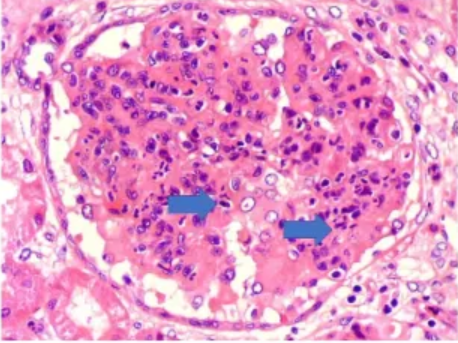

A

Proliferación endocapilar, celulas mesangiales.

- Lupus clase 2 o 3